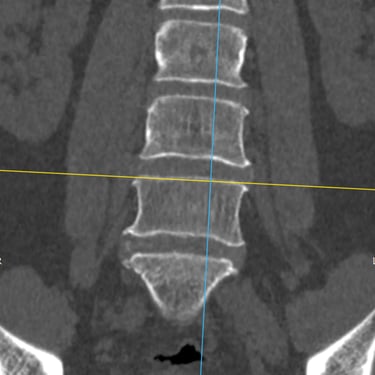

Inestabilidad de la Columna Lumbar: Tratamiento con Fijación Transpedicular y TLIF

La inestabilidad de la columna lumbar ocurre cuando los segmentos vertebrales pierden su alineación y soporte normal, generando dolor lumbar crónico, limitación funcional y, en algunos casos, compresión de las raíces nerviosas. Cuando el tratamiento conservador no resulta efectivo, la fijación transpedicular (FTP) asociada a la fusión intersomática transforaminal (TLIF) representa una alternativa quirúrgica eficaz. Este procedimiento permite estabilizar el segmento afectado, descomprimir las estructuras nerviosas y restaurar la biomecánica de la columna. La combinación de fijación y fusión reduce el dolor, mejora la estabilidad vertebral y favorece una recuperación funcional segura y progresiva.